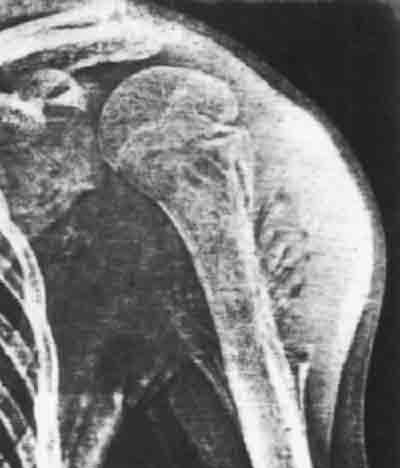

Магнитно-резонансная томография. В ходе этой процедуры получают трехмерные изображения, которые помогают различить злокачественные образования и здоровые ткани.